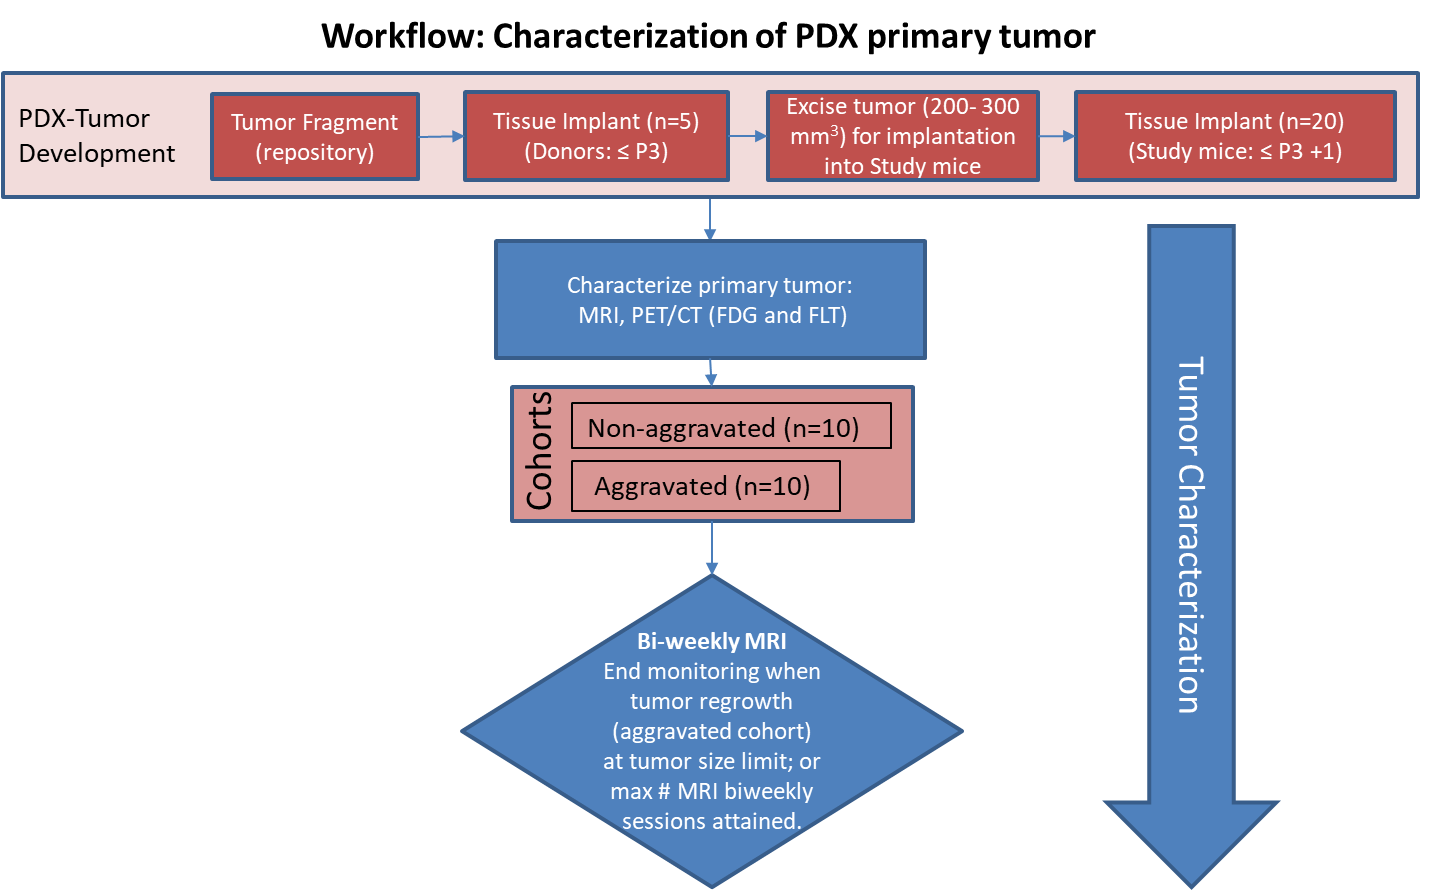

## PDMR-833975-119-R

| 名称 | 标注内容 | 类型 | 模态 | 数量 | 标签格式 | 文件格式 |

| - | - | - | - | - | - | - |

| [PDMR-833975-119-R](https://wiki.cancerimagingarchive.net/display/Public/Imaging+tissue+characterization+of+a+patient+derived+xenograft+model+of+adenocarcinoma+pancreas%3A+PDMR-833975-119-R) | 胰腺癌 | | MRI | 20 | | dcm |

[Aistudio下载](https://aistudio.baidu.com/aistudio/datasetdetail/64052)